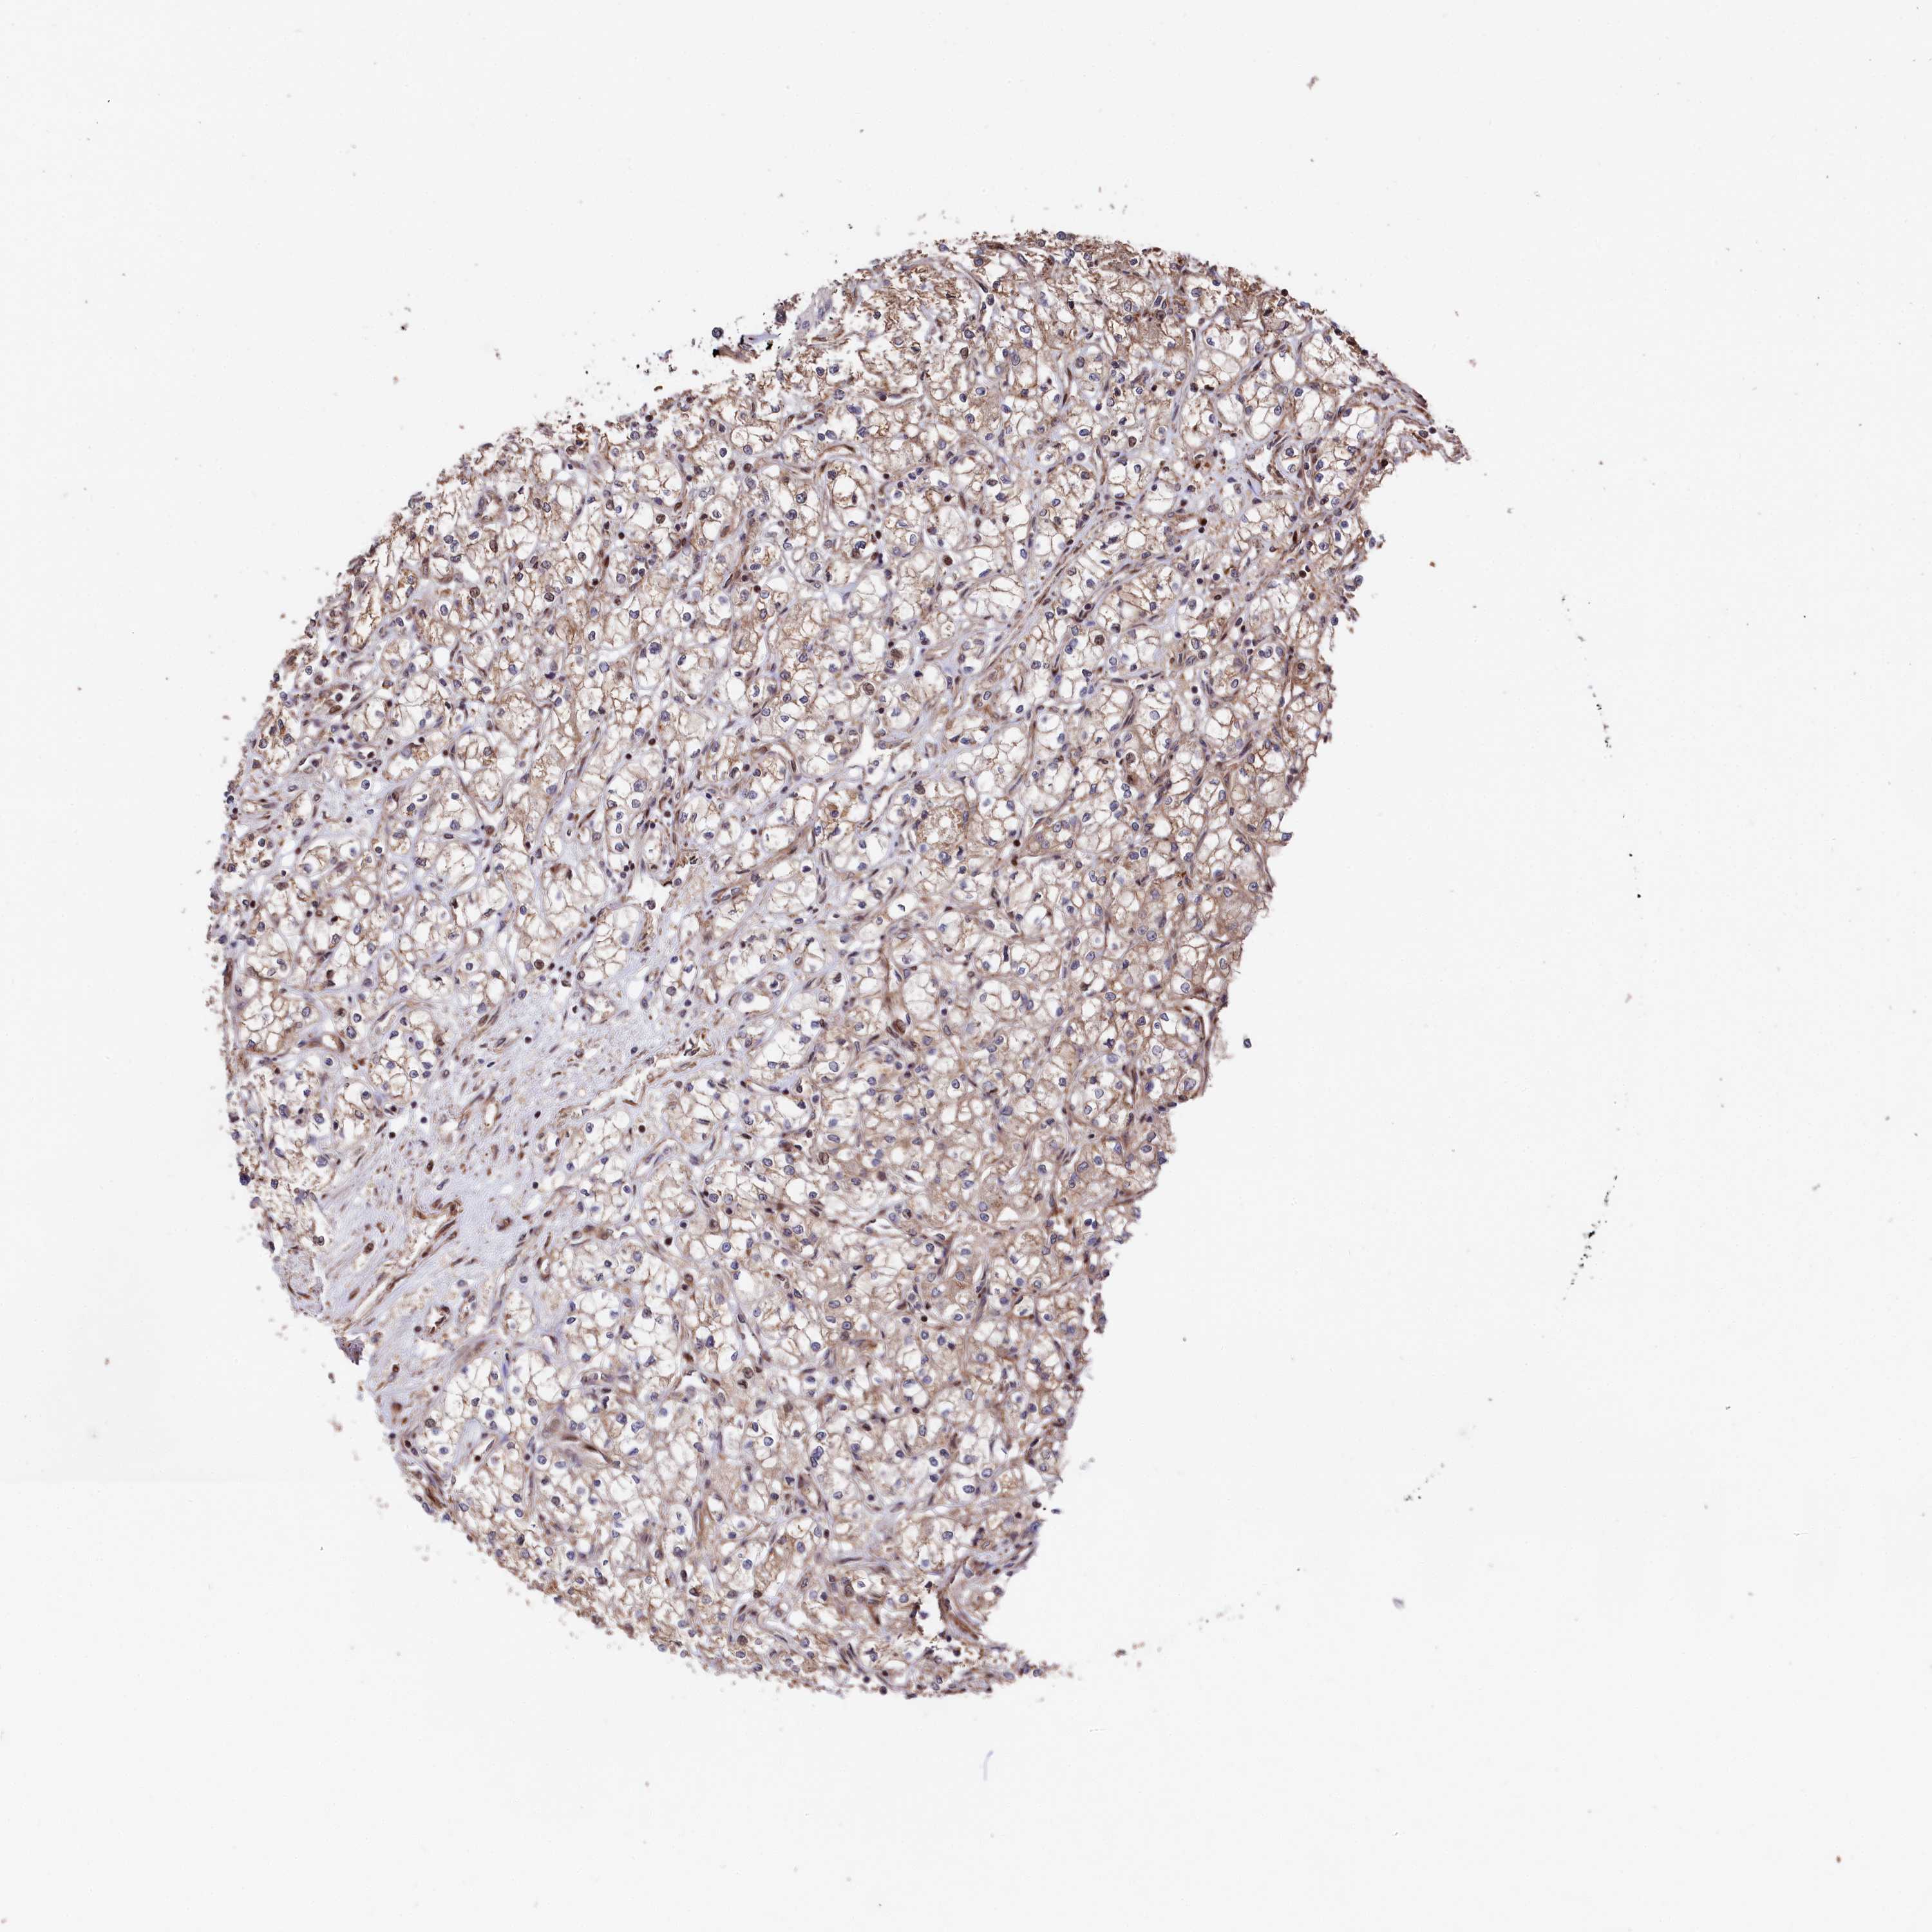

KIDNEY RENAL CLEAR CELL CARCINOMA (VALIDATION) - Interactive survival scatter ploti

The Survival Scatter plot shows the clinical status (i.e. dead or alive) for all individuals in the patient cohort, based on the same data that underlies the corresponding Kaplan-Meier plots. Patients that are alive at last time for follow-up are shown in blue and patients who have died during the study are shown in red.

The x-axis shows the expression levels (FPKM) of the investigated gene in the tumor tissue at the time of diagnosis. The y-axis shows the follow-up time after diagnosis (years). Both axes are complimented with kernel density curves demonstrating the data density over the axes. The top density plot shows the expression levels (FPKM) distribution among dead (red) and alive patients (blue). The right density plot shows the data density of the survived years of dead patients with high and low expression levels respectively, stratified using the cutoff indicated by the vertical dashed line through the Survival Scatter plot. This cutoff is automatically defined based on the FPKM cutoff that minimizes the p-score. The cutoff can be changed by dragging the vertical line or by entering a cutoff value in the square labeled "Current cut-off".

Under the Survival Scatter plot the p-score landscape (black curve; left axis) is shown together with dead median separation (red curve; right axis). Dead median separation is the difference in median mRNA expression between patients who have died with high and low expression, respectively. It is calculated as follows: median FPKM expression of dead patients with high expression - median FPKM expression of dead patients with low expression. This is intended to aid the user in visually exploring custom cutoffs and the associated p-scores and dead median separation.

Individual patient data is displayed and can be filtered by clicking on one or more of the category buttons on the top of the page. Categories describing expression level and patient information include: high, low, alive, dead, female, male and tumor stages. The scale of the x-axis can be toggled between linear and log-scale by clicking on the "x log" button. Mouse-over function shows TCGA ID, patient information and mRNA expression (FPKM) for each patient.

& Survival analysisi

Kaplan-Meier plots summarize results from analysis of correlation between mRNA expression level and patient survival. Patients were divided based on level of expression into one of the two groups "low" (under cut off) or "high" (over cut off). X-axis shows time for survival (years) and y-axis shows the probability of survival, where 1.0 corresponds to 100 percent.

TNKS1BP1 is not prognostic in Kidney Renal Clear Cell Carcinoma (validation)

Best expression cut offi

Based on the FPKM value of each gene, patients were classified into two groups and association between prognosis (survival) and gene expression (FPKM) was examined. The best expression cut-off refers the FPKM value that yields maximal difference with regard to survival between the two groups at the lowest log-rank P-value. Best expression cut-off was selected based on survival analysis .

When clicking on this number, the vertical dashed line indicating cut-off, the interactive survival plot, and the Kaplan-Meier curve will be adjusted to show results based on the best expression cut-off.

: 45.88

TCGA RNA samplesi

RNA-seq data is reported as average FPKM (number Fragments Per Kilobase of exon per Million reads), generated by the The Cancer Genome Atlas (TCGA) .

Normal distribution across the dataset is visualized with box plots, shown as median and 25th and 75th percentiles. Points are displayed as outliers if they are above or below 1.5 times the interquartile range. FPKM values of the individual samples are presented next to the box plot.

Average pTPM 38.7

Number of samples 100